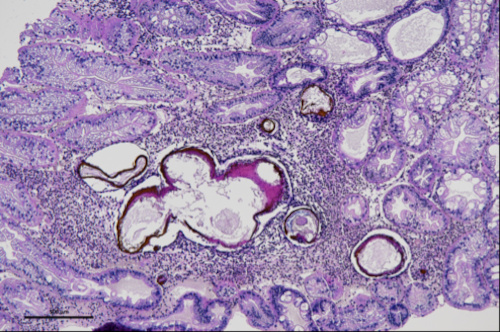

Katarina Bačnik, postdoc at National Institute of Biology (NIB), visited a lab at Istituto Zooprofilattico Sperimentale delle Venezie (IZSVe) in Legnaro, Padova, Italy from 10th to 15th August 2025, under the supervision of Dr. Tobia Pretto. The purpose of the visit was to provide education on sample preparation for histopathological analysis, processing of signal crayfish hepatopancreas samples, and designing a system for histopathological scoring of severity and frequency of observed histopathological changes, which was followed by examining samples under a microscope. Using high-throughput sequencing (HTS), we have previously characterized the virome of one of the most successful invasive freshwater invertebrate species in Europe—the crayfish (Pacifastacus leniusculus)—and identified novel and divergent RNA viruses associated with this species along its invasion range. Some of the viruses present in the invasive host can cause histopathological changes in tissues, as previously observed in the high incidence of idiopathic necrotizing hepatopancreatitis (Bekavac et al., 2022).

Using the newly obtained knowledge, we aim to implement the histopathological analysis of invertebrate samples in our lab at National Institute of Biology (NIB), in the case of hepatopancreas samples using the designed binominal scoring to describe the overall presence/absence of histological changes and ordinal method with scoring of several test fields.